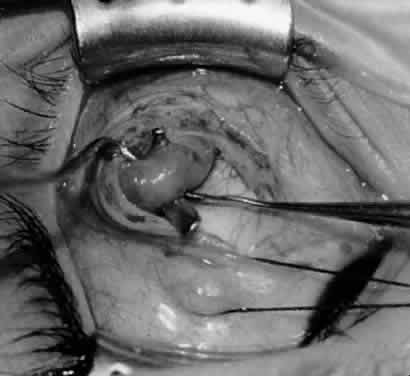

Fig. 5. The Stevens hook is placed adjacent to the posterior edge of the inferior oblique muscle and rotated as the inferior oblique muscle is drawn into the operative field. A forceps is used to retract the redundant Tenon's capsule, encapsulated fat, and intermuscular septum as the muscle is drawn further into the operative field with the Stevens muscle hook.

Fig. 6. The Westcott scissor is used to open the intermuscular septum along the posterior border of the inferior oblique muscle. Care is taken to cut adjacent to the tip of the Stevens muscle hook. This incision is important because it helps to avoid damaging the Tenon's capsule and releasing fat, which leads to the adherence syndrome and postoperative hypotropia.

Fig. 7. A Westcott scissor is used gently to open a space beneath the elevated inferior oblique muscle and allow placement of a Green muscle hook.

Fig. 8. The Green muscle hook is placed beneath the belly of the inferior oblique muscle, and the eye is retracted nasally.

Fig. 9. A Westcott scissor is used to dissect the intermuscular septum and expose the insertion of the inferior oblique muscle.

Fig. 10. The inferior oblique muscle is placed on the Green muscle hook. The exposed insertion is ready for myotomy, myectomy, disinsertion, placement of sutures for recession, or removal for the extirpation procedure.

Fig. 11. Sutures are placed into the insertion of the inferior oblique muscle before it is sectioned from the globe for the recession procedure.